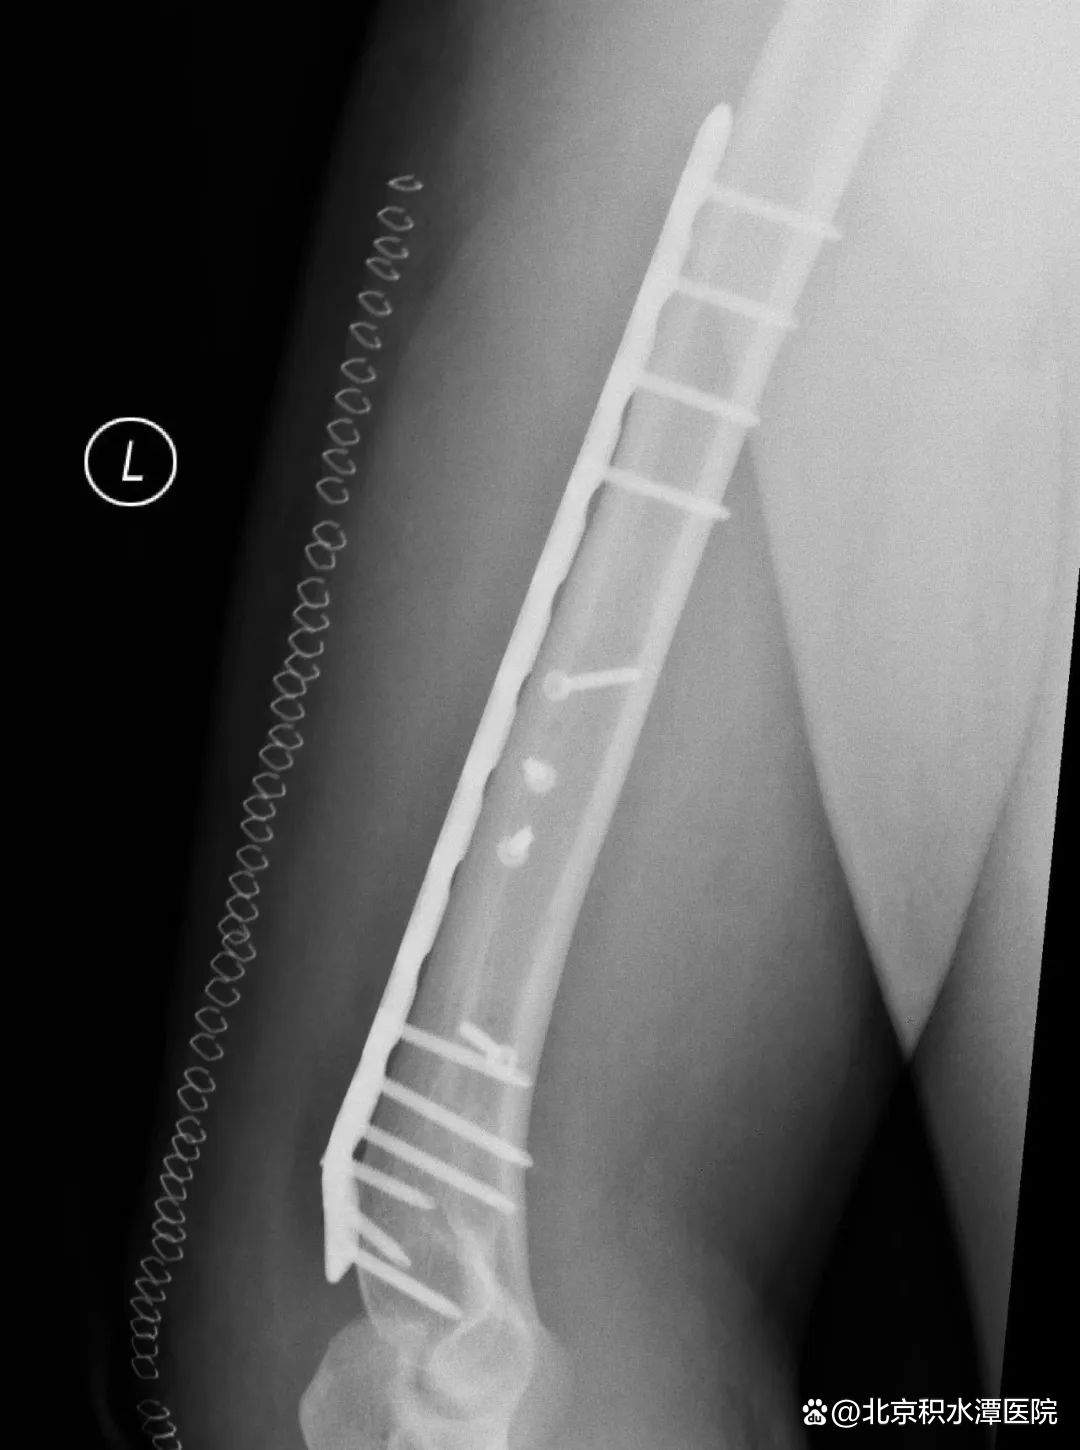

图|扳手腕导致的肱骨干骨折

由于存在共同的受伤机制,扳手腕导致的肱骨干骨折表现极为相似。这类骨折几乎都是肱骨远端三分之一螺旋形骨折,半数伴有蝶形骨折片,在AO/OTA分型中分别为12-A1型和12-B1型,可伴有桡神经损伤。

图|切开复位钢板螺钉内固定术